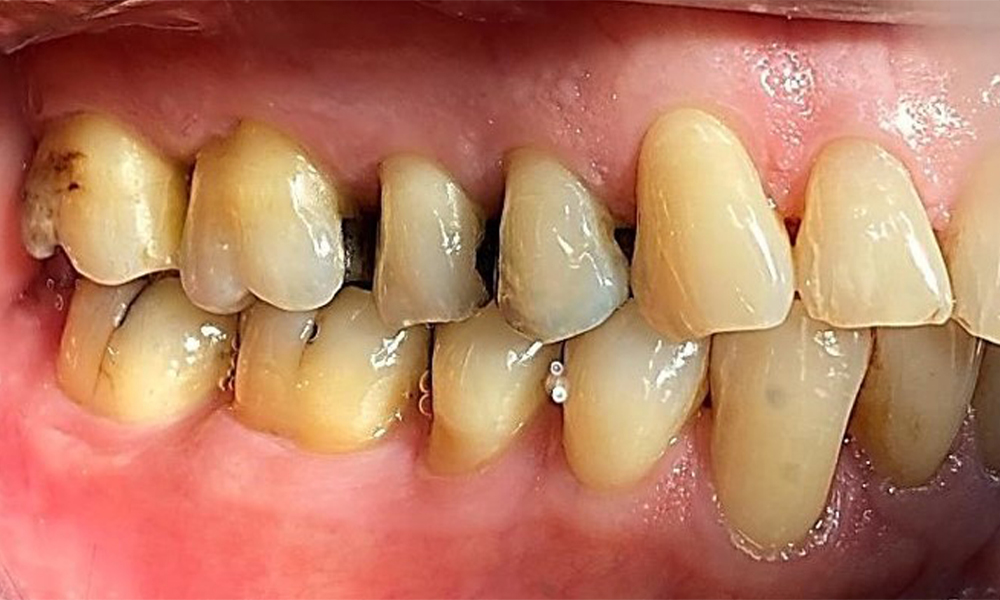

Right lateral view. Loss of the interdental papillae.

Fig. 3 Right lateral view. Loss of the interdental papillae. © Dr R. Krapf

Periodontal findings

The patient has stage II, grade B periodontitis (5). At 1 to 3 mm, the clinical probing depths were within the physiological range. Localized probing depths of 5 mm were observed on the mesiopalatal aspects on both 17 and 27. There are generalized recessions of 1–3 mm with partial loss of the interdental papillae (Fig. 2, Fig. 3, Fig. 4)